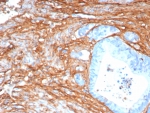

Immunohistochemistry of Periostin antibody in human lung tissue. Formalin-fixed, paraffin-embedded human lung was stained with recombinant monoclonal Periostin antibody (clone POSTN/8523R) following heat-induced epitope retrieval by boiling in pH 9 10 mM Tris with 1 mM EDTA for 20 minutes and cooling prior to testing. HRP-DAB brown chromogenic signal highlights extracellular matrix and stromal regions along alveolar septa and peribronchial connective tissue, consistent with the secreted and matrix-associated localization of Periostin. The inset image shows PBS in place of the primary antibody as a secondary-only negative control, demonstrating minimal non-specific background staining.

IHC staining of FFPE human colon tissue with recombinant Periostin antibody (clone POSTN/8523R). HIER: boil tissue sections in pH 9 10mM Tris with 1mM EDTA for 20 min and allow to cool before testing.